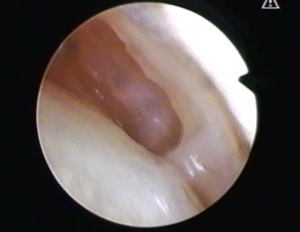

Ecco come si vede dentro l’articolazione : si pulisce

Si taglia il tendine

Eccolo tagliato